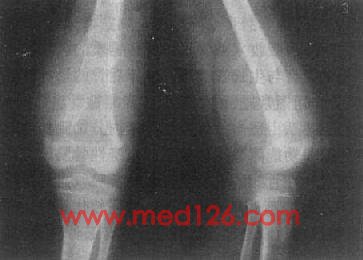

骨巨细胞瘤以20~40岁为常见,好发于四肢长骨,以股骨下端、胫骨上端和桡骨下端为常见。主要临床表现为局部疼痛、肿胀和压痛。较大肿瘤可有局部皮肤发热和静脉曲张。

长骨巨细胞瘤的X线表现多较典型(图2-1-23),常侵犯骨端,症变直达骨性关节面下。多数为偏侧性破坏,边界清楚。瘤区X线表现可有两种类型,较多的病例破坏区内可有数量不等、比较纤细的骨嵴。X线上可见似有分隔成为大小不一的小房征,称为分房型。少数病例破坏区内无骨嵴,表现为单一的骨质破坏,称为溶骨型。病变局部骨骼常呈偏侧性膨大,骨皮质变薄,肿瘤明显膨胀时,周围只留一薄层骨性包壳。肿瘤内无钙化或骨化致密影,邻近无反应性骨膜增生。边缘亦无骨硬化带,如不并发骨折也不出现骨膜增生。破坏区骨性包壳不完整,并于周围软组织中出现肿块者表示肿瘤生长活跃。肿瘤边缘出现筛孔状和虫蚀状骨破坏,骨嵴残缺紊乱。侵犯软组织出现明确肿块者,则提示为恶性骨巨细胞瘤。肿瘤一般不穿破关节软骨,但偶可发生,甚至越过关节侵犯邻近骨骼。